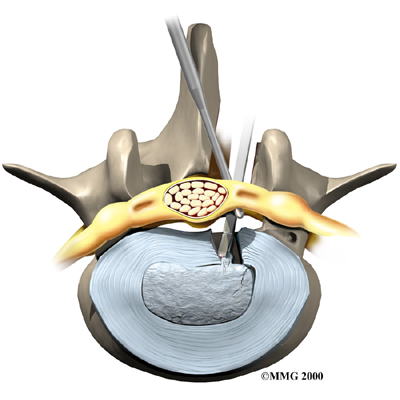

Microdiscectomy

Microdiscectomy is becoming the standard surgery for lumbar disc herniation. The procedure is used when a herniated disc is putting pressure on a nerve root. It involves carefully taking out part of the problem disc (discectomy). By performing the operation with a surgical microscope, the surgeon only needs to make a very small incision in the low back. Categorized as minimally invasive surgery, this surgery is thought to be less taxing on patients. Advocates also believe that this type of surgery is easier to perform, that it prevents scarring around the nerves and joints, and that it helps patients recover more quickly.

Related Document: FYZICAL Mooresville Town Square's Guide to Lumbar Discectomy